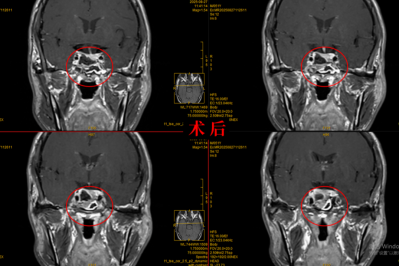

不用开颅,微创切除脑肿瘤